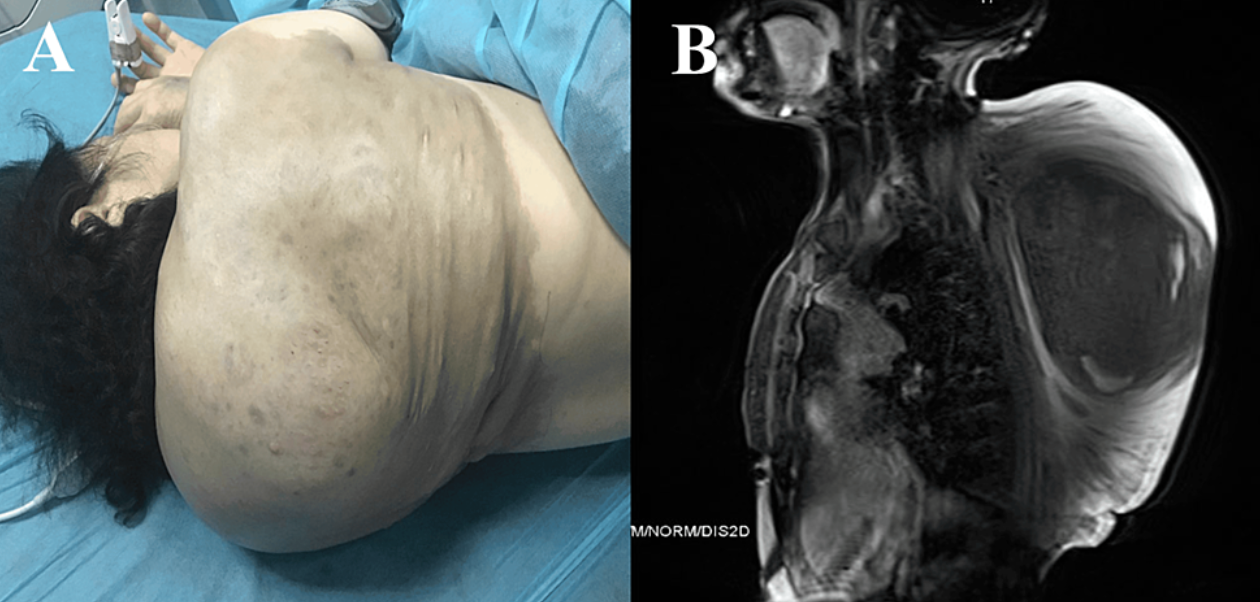

Pseudohump Gallery Pseudohump By Nicole Angemi|2025-05-21T09:06:56-04:00October 28th, 2023|The Gross Room, MEDICAL, Genetic, Tumors & Cysts| Read More 7